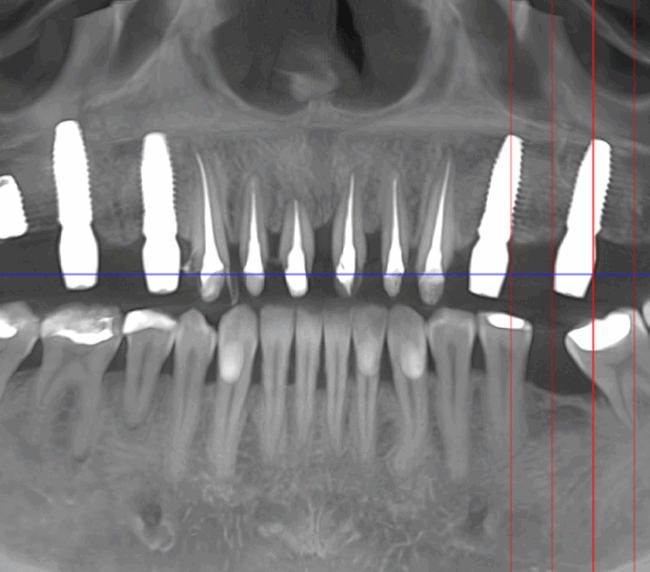

Reabilitarea complexă în stomatologie presupune refacerea completă a sistemului dentoalveolar, atât din punct de vedere funcțional, cât și estetic. Procesul începe cu o examinare detaliată a cavității bucale, interpretarea investigațiilor imagistice (CBCT), evaluarea musculaturii, articulațiilor temporomandibulare și a parametrilor estetici.

Tomografii (CBCT)

Caz 2